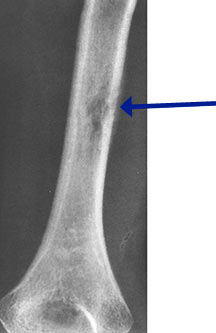

- May arise from any bone and any site within a bone (epiphyseal, metaphyseal, diaphyseal)

- Radiographically variable appearance: may appear benign (geographic) or malignant (permeative or moth eaten)

- Curettage and bone grafting for long bones and weight bearing bones at risk for fracture